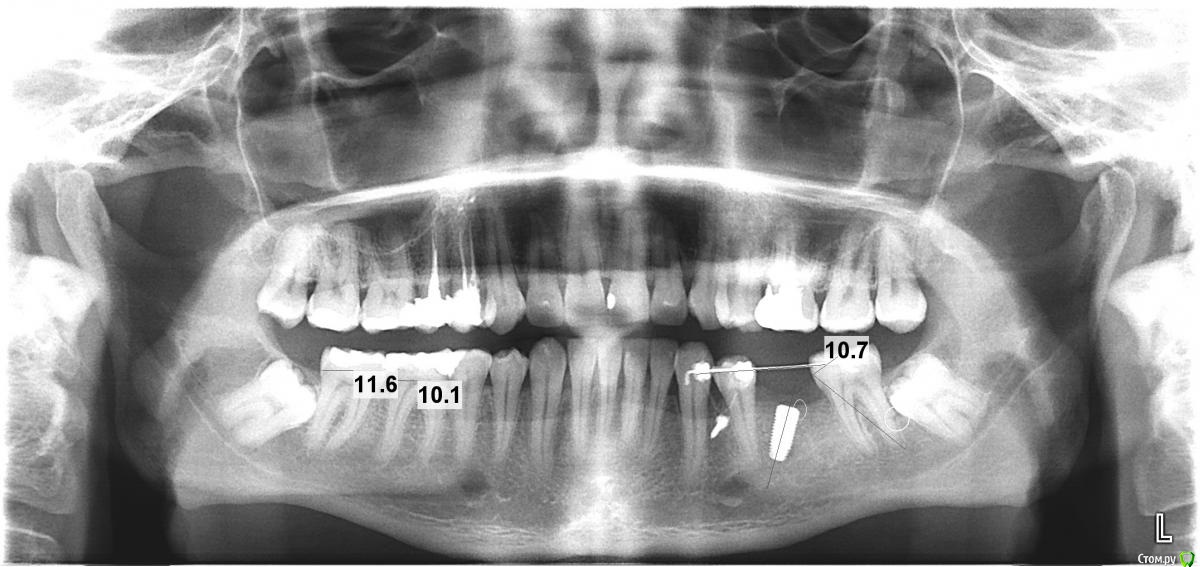

vadimanf Опубликовано 23 октября, 2015 Поделиться Опубликовано 23 октября, 2015 Здравствуйте! Около 5-ти месяцев назад установил имплант. На этой неделе сделали снимок и визуально видно что он стоит криво. Врач говорит, что угол в пределах нормы. Какие возможны негативные последствия при таком угле на жевательном зубе? Ссылка на комментарий

faity Опубликовано 23 октября, 2015 Поделиться Опубликовано 23 октября, 2015 все решается индивидуальными аббатментами, проблемы нет 2 Ссылка на комментарий